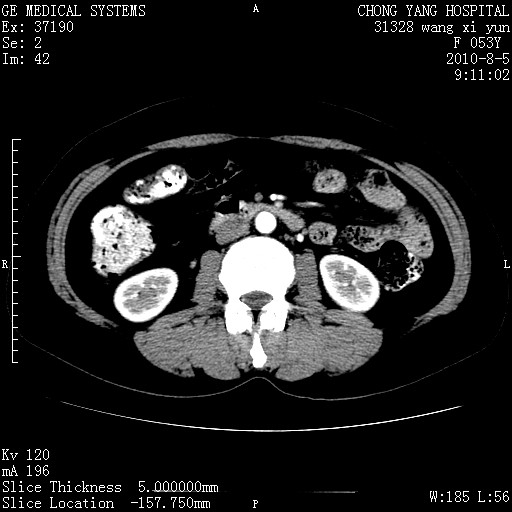

标题: CT28214:F41Y 血尿二十天,建议盆腔平扫加增强。

1)考虑肝左叶胆管细胞癌。2)脂肪肝。